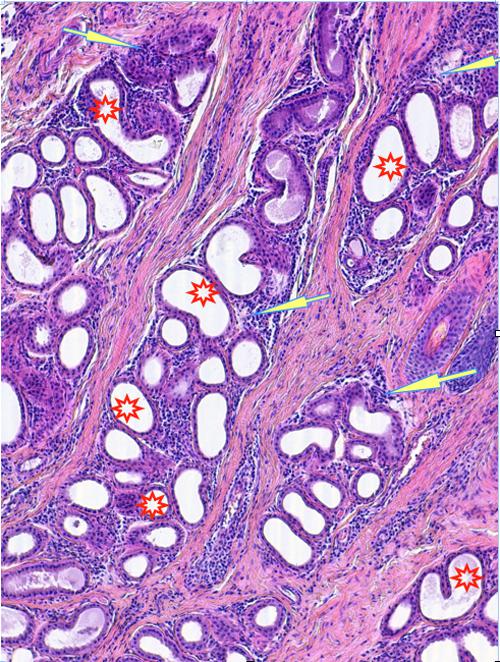

Photo 2 (Hémalun Eosine X 100) peau velue : Vue rapprochée de la Photo 1,

sur un infundibulum folliculaire criblé de pustules pariétales microloculaires.

On note une hyperkératose orthokératosique de l’infundibulum adjacent.

Légendes de la Photo 2 :

- Double flèche bleue pointillée : grand axe des infundibula folliculaires

- Double flèche verte : derme

- Étoiles rouges pleines : erreur (!)

- Ovales jaunes : pustules folliculaires pariétales (folliculite murale)

- Étoiles vertes évidées : lumière des follicules pileux, à gauche parakératosique, à droite orthokératosique

Photo 3 (Hémalun-Eosine X100) peau velue : Les infundibula folliculaires sont le siège d’une acanthose irrégulière et d’une hyperkératose (avec alternance d’ortho et de parakératose). Leur abouchement est souvent obstrué d’un matériel pustuleux. Leur gaine épithéliale externe présente des lignes de fissuration et de lyse des attaches desmosomiales des cellules épithéliales, dans lesquelles s’immiscent des granulocytes.

Légendes de la Photo 3 :

- Ovales jaunes : pustules obstruant l’ostium ou l’infundibulum

- Flèches jaunes : fissuration linéaire dans la gaine épithélilae externe d’un follicule parallèle au grand axe de l’infundibulum

- Étoiles vertes évidées : hyperkératose orthokératosique

- Étoiles rouges pleines : hyperkératose parakératosique

- Étoiles turquoises pleines : infiltrat inflammatoire dermique périvasculaire à diffus